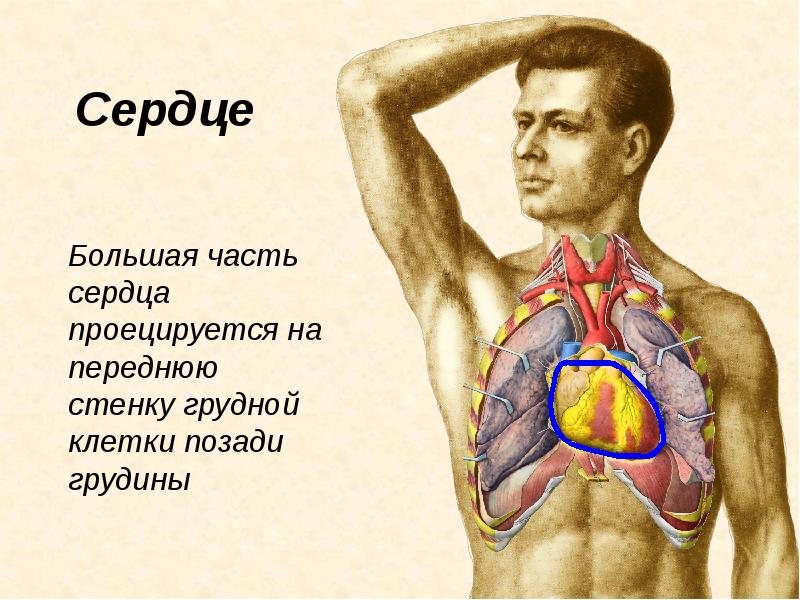

Сердце у человека располагается в грудной полости.

Расположение сердца у человека.

Анатомическое расположение сердца.

Сердце в грудной клетке расположено.

Где расположено сердце у человека анатомия.